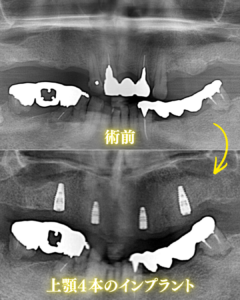

X線写真治療前後比較

上顎には、均等な間隔で綺麗な方向にインプラントが入ってるのが分かります。